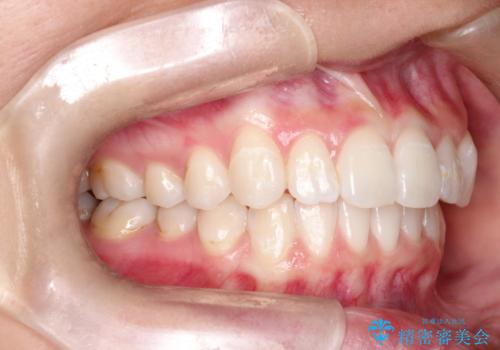

前歯の突出、深い噛み合わせ、ガタつきをマウスピース矯正(インビザライン)で治療した症例

- 初診時には上顎前歯の突出、前歯部の深いかみ合わせ、叢生が見られる状態でした。

このケースでは非抜歯にて奥歯を後方に移動させる事で前歯の突出を改善するスペースを作り出していますが、これはマウスピースと顎間ゴムの併用によるもので、患者様のご協力の賜物と言えます。

深い噛み合わせについてはシミュレーション上の結果と、予期される実際の歯の移動量とを考慮し、特殊なセットアップを行う事で望ましい結果を得ることができました。